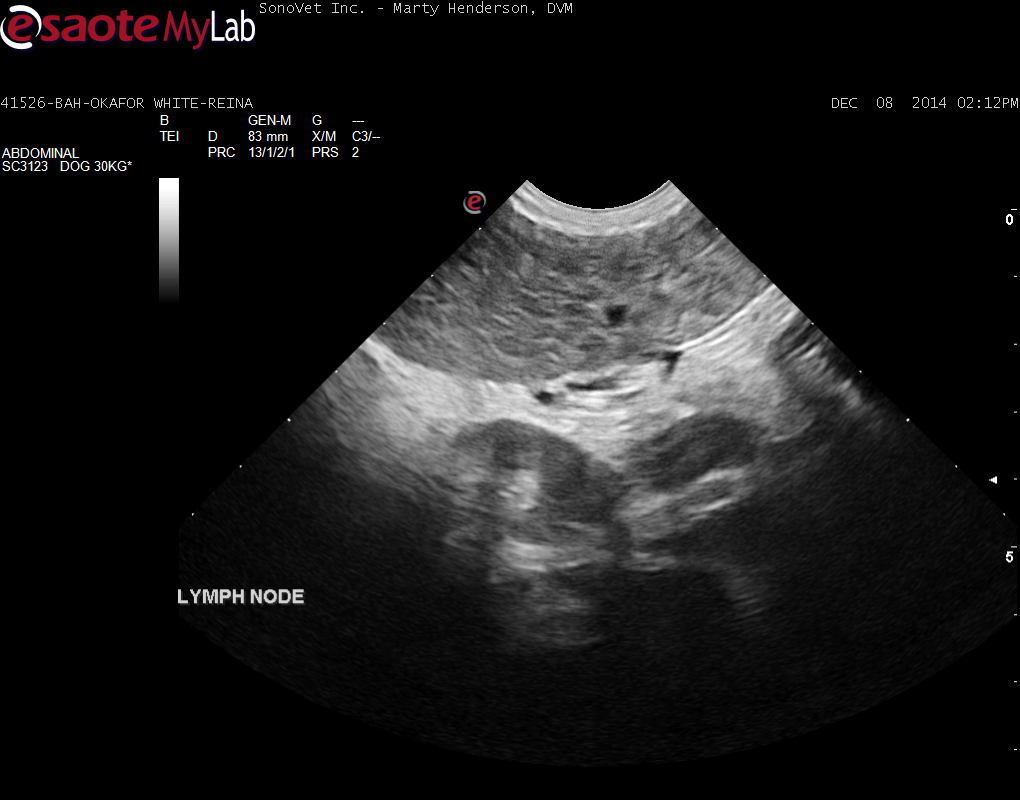

A 6-year-old female Labrador was presented for evaluation of loose stools and weight loss. Abnormalities on serum biochemistry were elevated liver enzyme activity and hypoalbuminemia. On survey thoracic radiographs, a mild interstitial pulmonary pattern was evident.